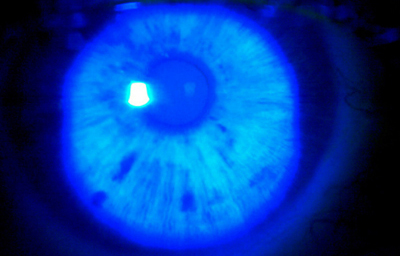

Efélides, se pueden discriminar mejor con filtro azul.

Archivo Fotográfico Dr. Carmen Barraquer